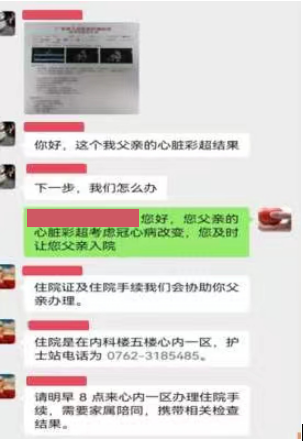

冠心病介入“日间病房”预约

通过现代科技进行有效沟通,能精准和灵活的安排流程

冠心病介入“日间病房”住院服务在“一站式优质服务”的基础上,完善院前服务功能,开展“一站式”院前服务;管理服务下沉,主动对接日间病房及手术需求,优化日间手术患者院前检查流程;保障日间手术的围手术期安全,提高了医院运行效率,提升了患者就医体验。